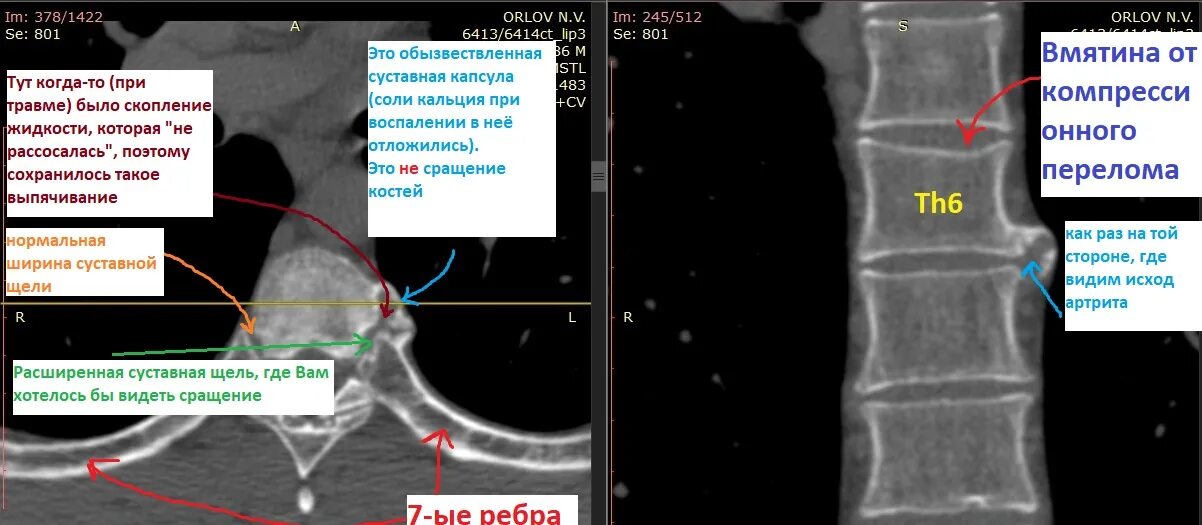

Сакроилеит на кт